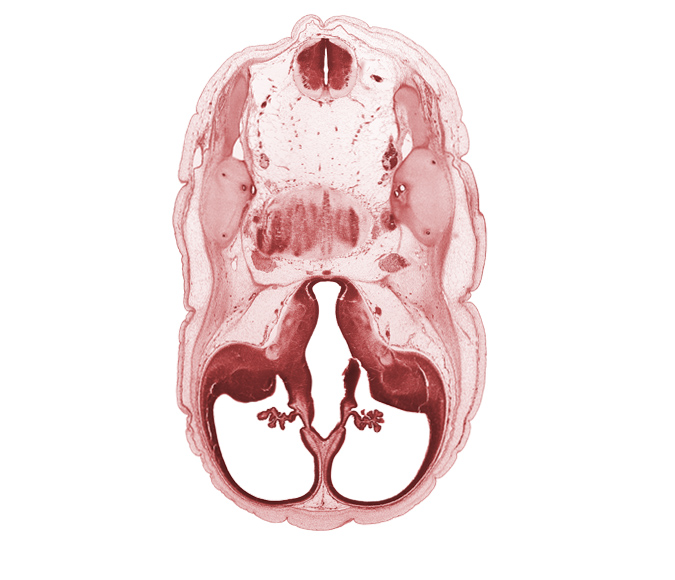

Carnegie Embryo #4090 | Location: 7-11

Keywords: accessory nerve (CN XI), anterior semicircular duct, basilar artery, cerebral vesicle (hemisphere), common crus, edge of interventricular foramen, facial nerve (CN VII), glossopharyngeal nerve (CN IX), lateral ventricle, lateral ventricular eminence (telencephalon), posterior communicating artery, posterior semicircular duct, third ventricle, vagus nerve (CN X), vestibulocochlear nerve (CN VIII)

Source: The Virtual Human Embryo.